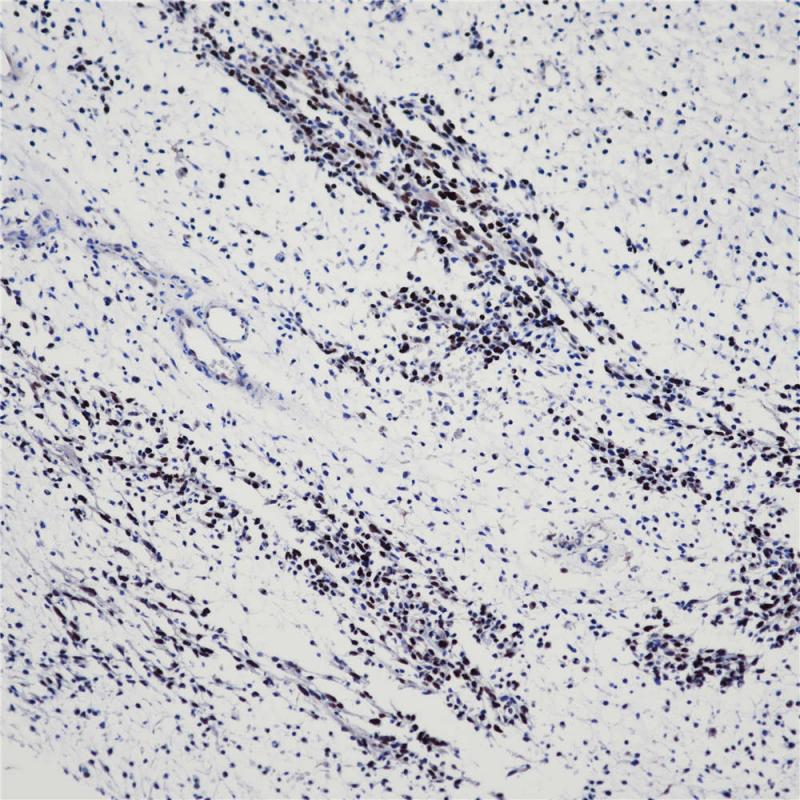

平滑肌肌球蛋白重链是平滑肌细胞浆内的结构蛋白,与平滑肌收缩功能相关。在平滑肌早期发育阶段即有表达,常用于间叶肿瘤的诊断和分类。也可用于乳腺肌上皮细胞的检测,有助于鉴别乳腺原位癌与浸润癌。

阳性对照

子宫肌瘤